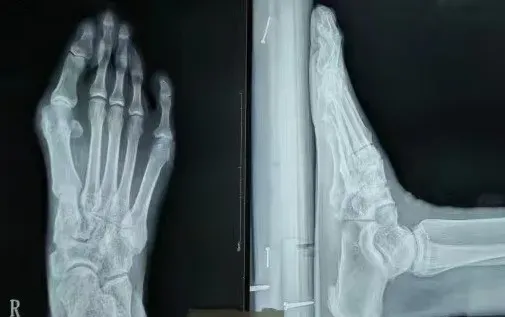

上图为分析患者的患病情况

上图为术前术后对比图

术前术后X光片对比图